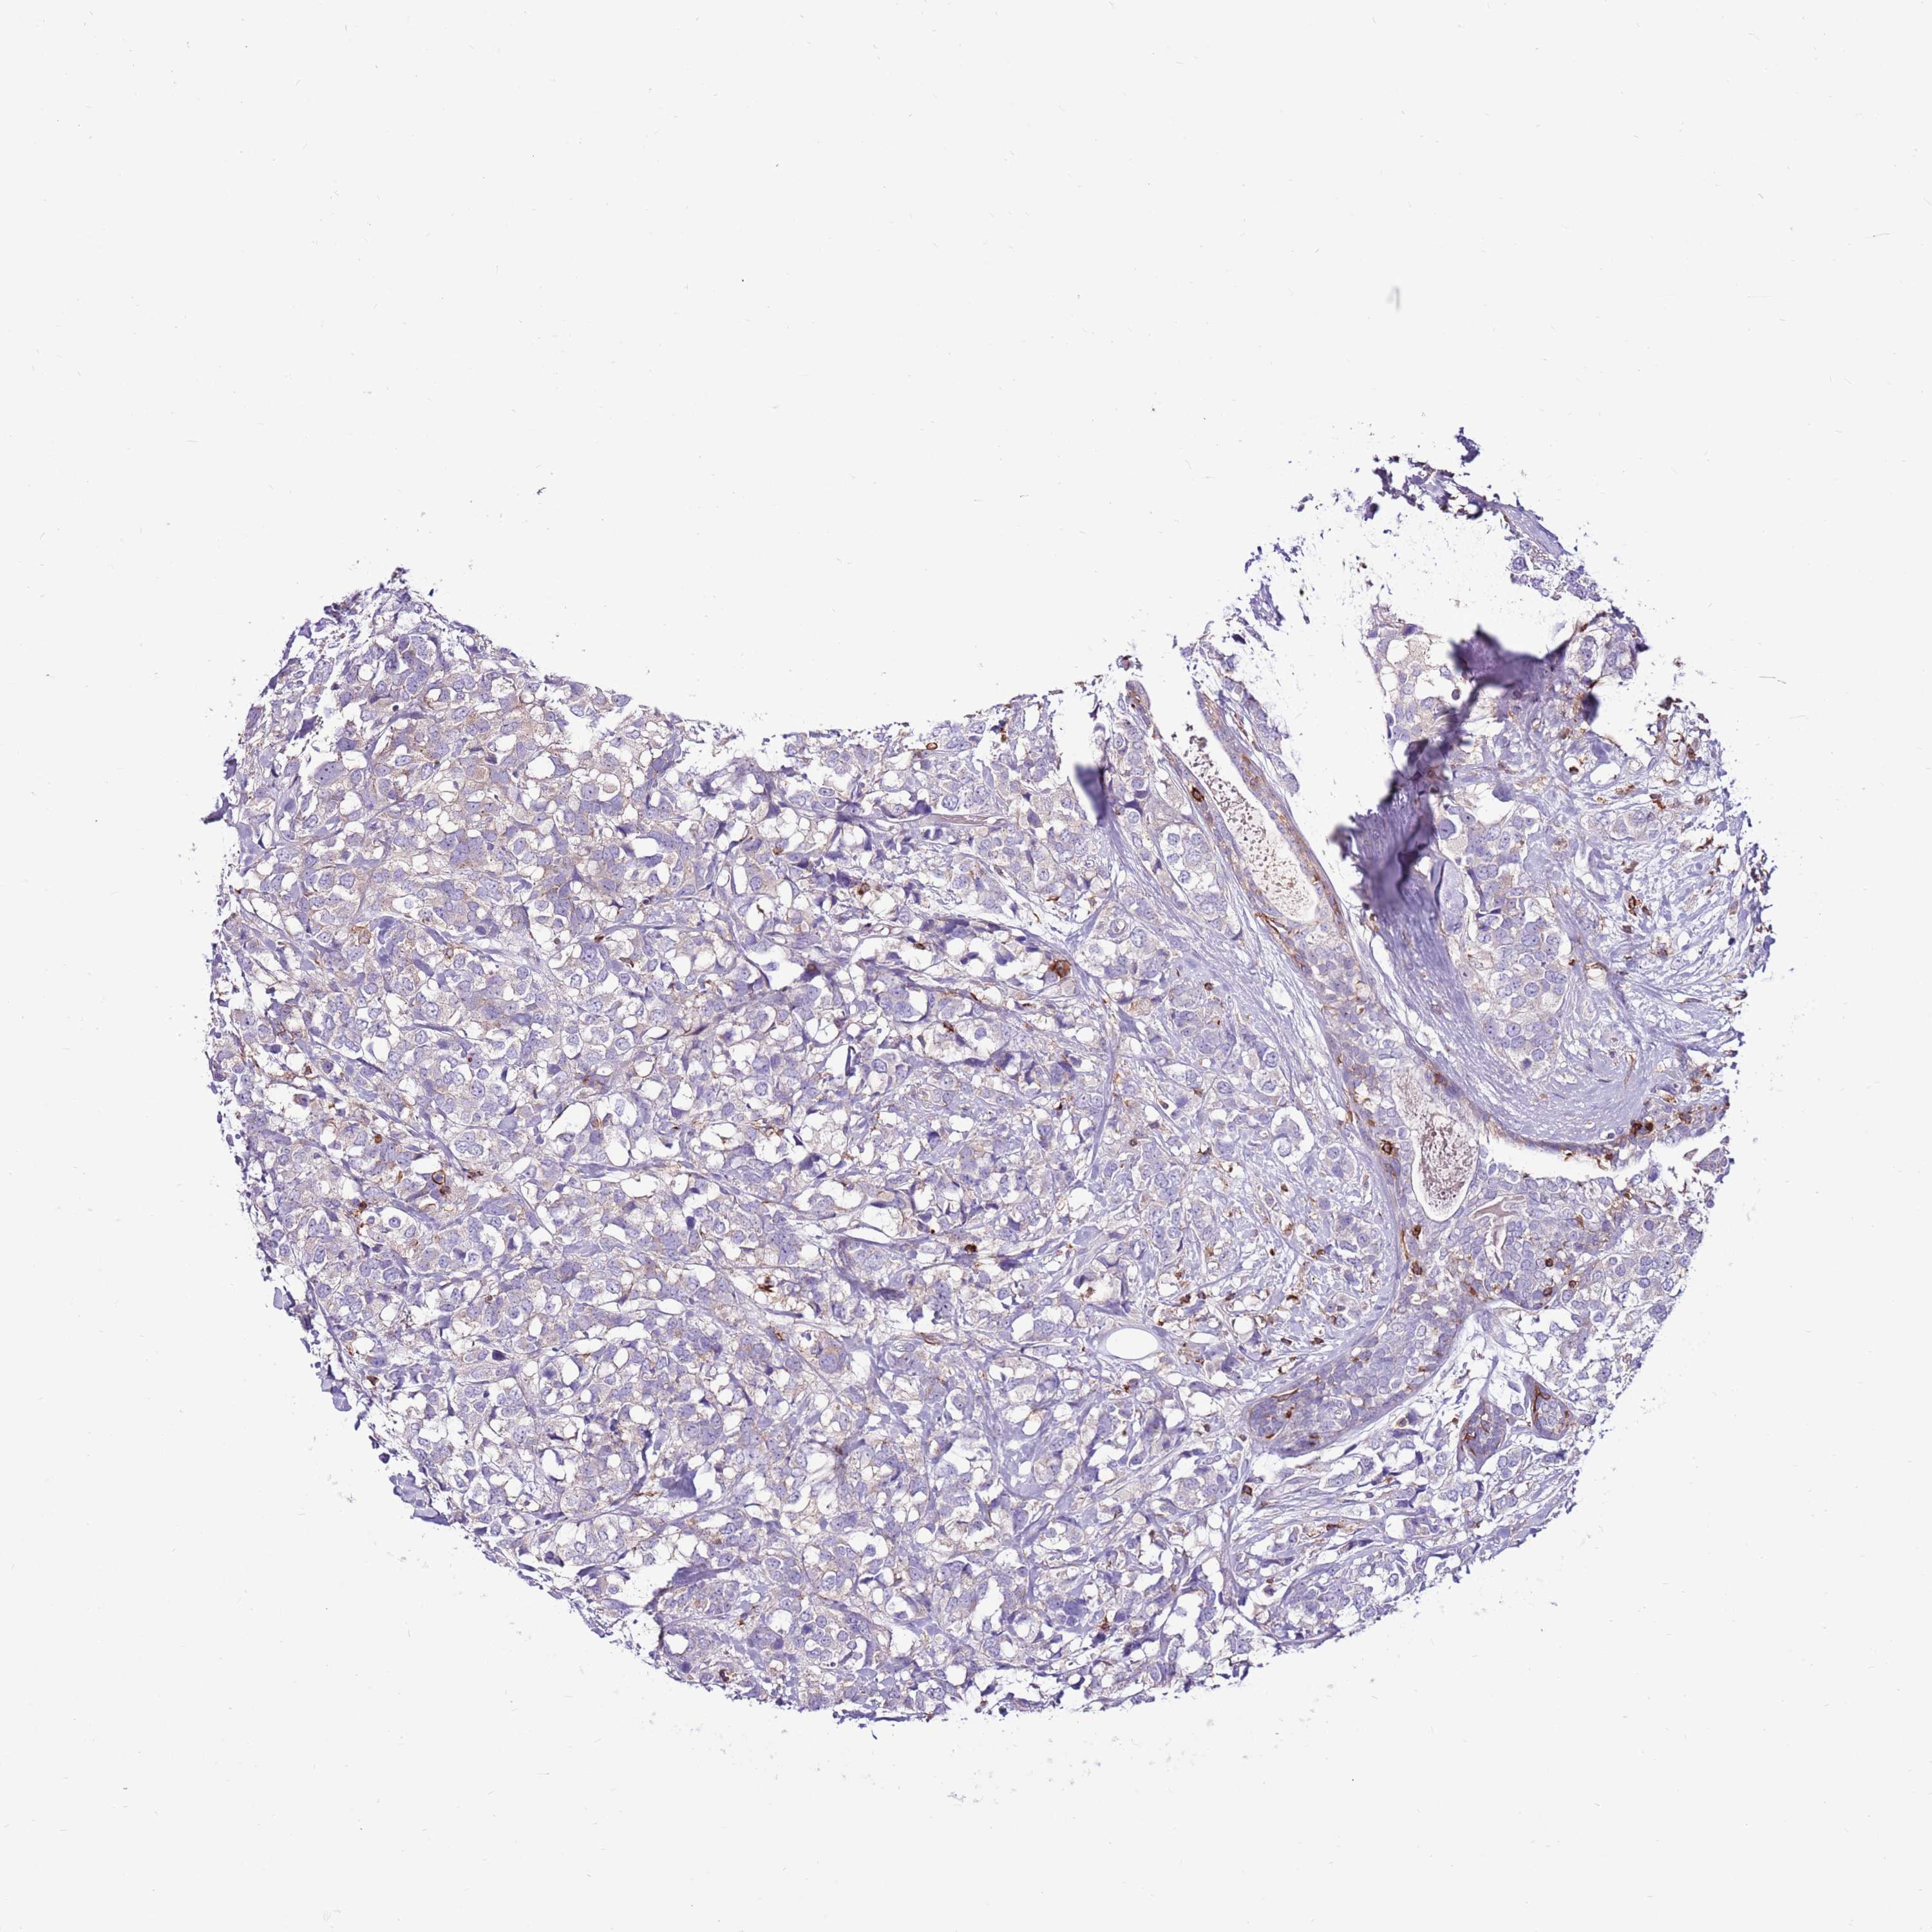

BRCA TCGA BRCA VALIDATION PROTEIN EXPRESSION

ANTIBODIES

AND

VALIDATION